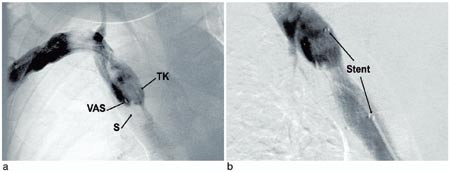

Behandling og forløp. Trombolysekateter (5F Jetlysis, Angiomed, BardInc, Karlsruhe, Tyskland) ble først lagt inn fra høyre arm, og det ble gitt alteplase 1 mg/t og samtidig heparininfusjon i trombolysekateteret. Bolusdose av alteplase ble ikke anvendt, da pasienten var antikoagulasjonsbehandlet med warfarin. Venografi etter ett døgn viste fin rekanalisering av høyresidige overarmsvener og delvis rekanalisering av de venstresidige overarmsvener samt v. cava superior. En subtotal stenose i v. cava superior ble avdekket (fig 2 a). Lumen i det stenoserte området hadde en diameter på 2 – 3 mm, og spissen av shunten endte i dette området (fig 2 a). Det ble satt inn en stent (14 x 40 mm Symphoni stent, Boston Scientific, USA) som ble dilatert til 10 mm (fig 2 b). Trombolysekateter ble så lagt inn fra venstre arm, og det ble gitt infusjon av alteplase og heparin. Venografikontroll viste komplett trombolyse etter totalt to døgns trombolytisk behandling. Pasienten ble behandlet med lavmolekylært heparin og warfarin inntil INR hadde vært i terapeutisk område (2,5 – 3,5) i to døgn. Ved utskrivning to uker etter innleggelse var pasienten fullstendig restituert. Ved kontroll etter seks måneder var han klinisk i fin form, og venografi viste åpne vener.

Behandlingseffekt ved lokal trombolytisk behandling evalueres med daglig venografi. Dette vil kunne avdekke anatomiske forhold som disponerer for trombosering og umiddelbart være tilgjengelig for intervensjon. Hos vår pasient ble det påvist stenose i v. cava superior, som ble dilatert og stentet. Intervensjonen med dilatasjon og stenting vil sannsynligvis være svært viktig for å unngå ny trombose i det aktuelle området.